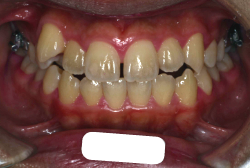

「歯並びの凸凹を直したい」という主訴で来院したケースです。診断の結果、たしかに「叢生」という隙間が足りないと言うことが原因の凸凹症例でした。

しかし、それ以上に問題なのは「前歯の噛み合い方が深すぎる」という症状で、初診の歯の正面写真を見ると下の前歯が全く見えません。こういう症状を矯正学では「過蓋咬合(かがいこうごう)」と言います。過蓋咬合を放置すると、将来的に顎関節に悪影響を与えるとされており、顎関節症の原因因子の一つです。また下の前歯の先端が、上の前歯の裏側の歯茎と強く接触するため、歯周病の原因にもなります。

検査の結果、凸凹が軽症なため非抜歯で矯正すること可能と判断、マルチブラケット装置にて治療しました。治療後は歯並びが綺麗になっただけでなく、噛み合わせ的にも正しい状態が確立しています。